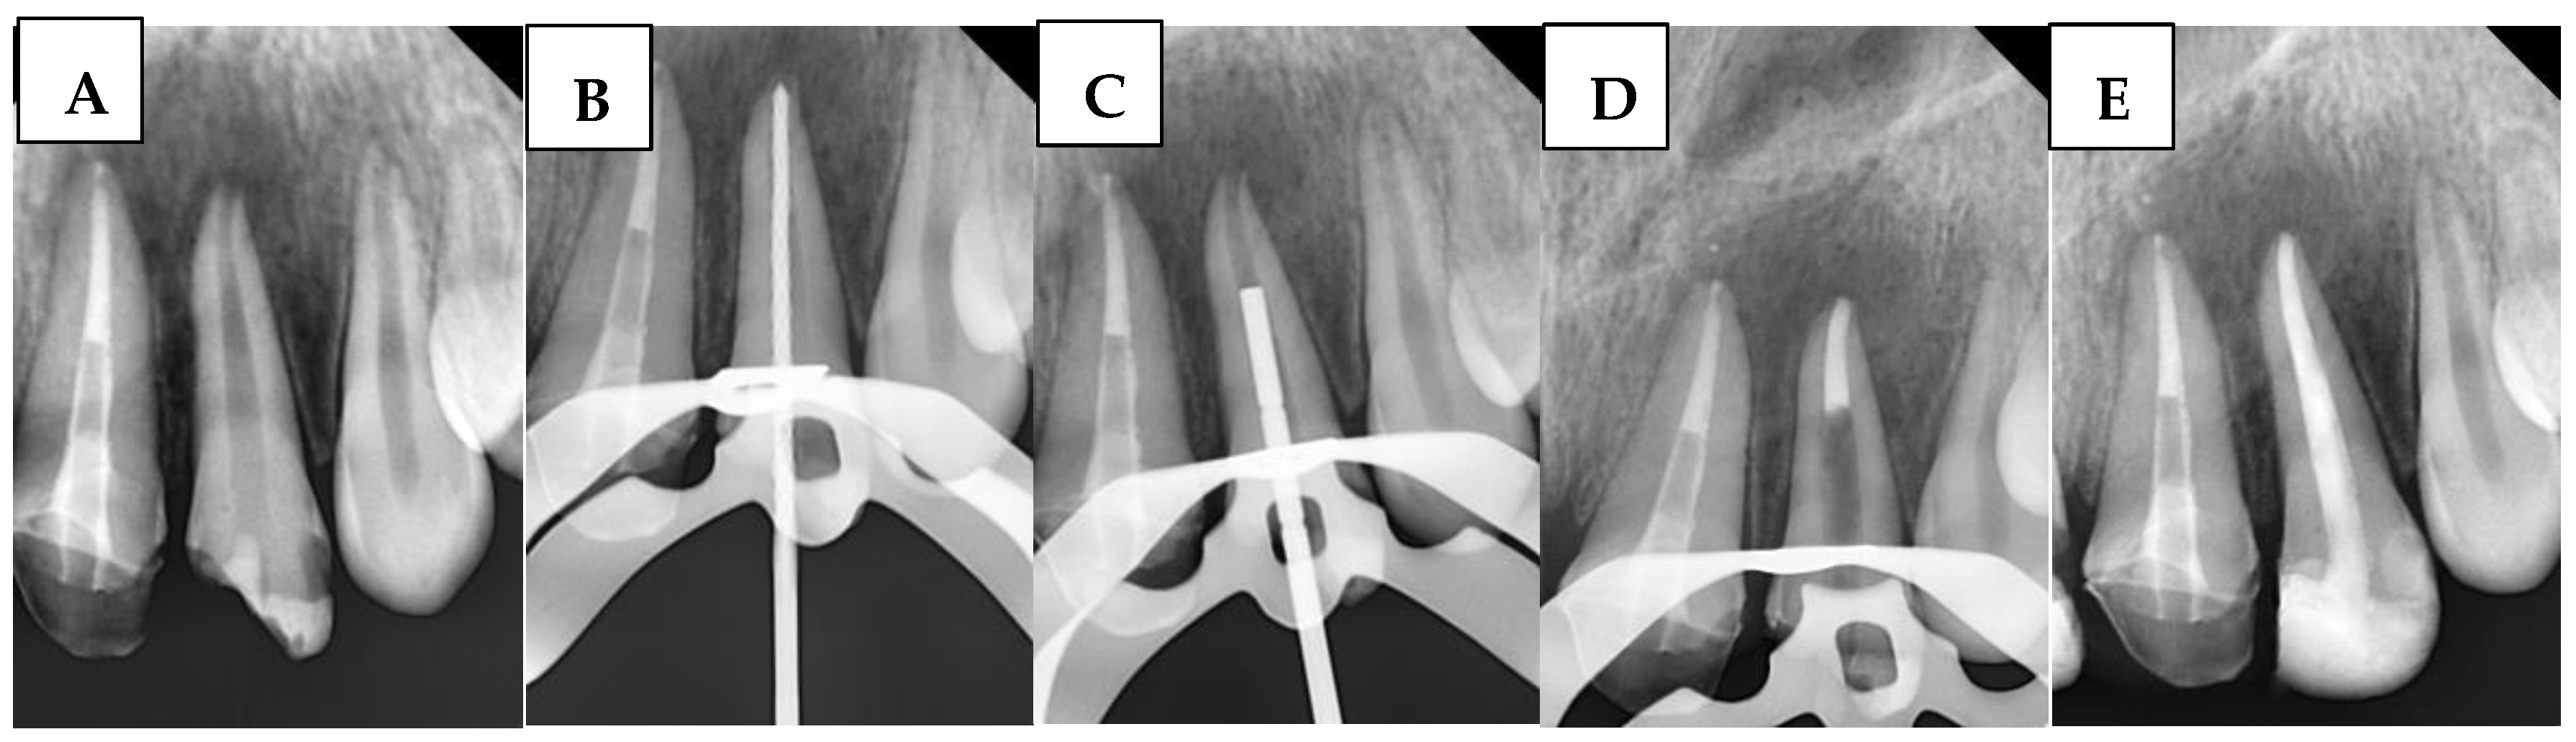

2.6.3. Bioceramic Putty Apical Plugs (BPAP) Group

A radiograph was first taken with the hand plugger to ensure that it reached 4 mm short of the radiographic apex, as specified by the WL. The BioCeramic Putty (BP) (TotalFill® BC RRM™, FKG Dentaire, Le Crêt-du-Locle, Switzerland) was applied to the apical 4 mm of the canal using a modified cannula [34], with placement adapted using a hand plugger and confirmed radiographically. Any BioCeramic extrusion was recorded at this stage in the DPF. The incisors were then temporized with a cotton pellet and glass ionomer filling. The following day, after isolation and removal of the temporary filling and cotton pellet, the remaining canal space was obturated with gutta-percha and BioCeramic Sealer (BS) (TotalFill® BC Sealer™, FKG Dentaire, Le Crêt-du-Locle, Switzerland) using the cold lateral condensation technique. A periapical radiograph confirmed that the canal was obturated without voids or gaps. Figure 2 illustrates the steps of the procedure in the BPAP group.

Figure 2. Sequential steps of the procedure in the BPAP group: (A) Preoperative periapical radiograph, (B) Working length radiograph, (C) Plugger fit, (D) Apical plug formation, and (E) Postoperative radiograph.